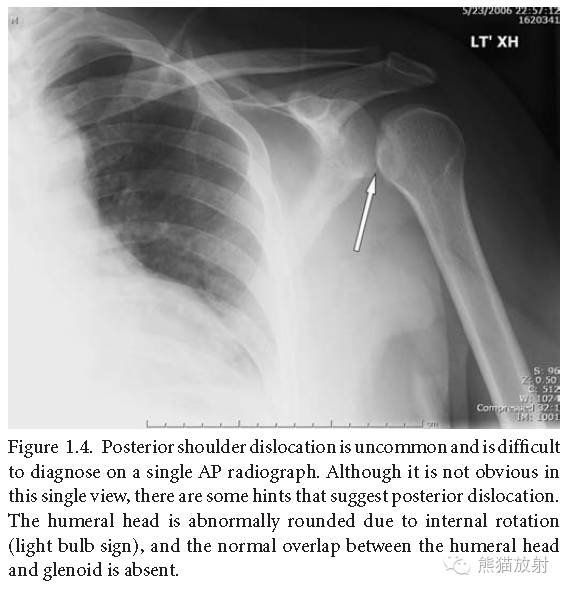

肩关节后脱位:不常见,单凭正位片很难诊断,尽管不明显,但有一些发现可提示后脱位,肱骨头由于内旋形态异常(呈“灯泡征”),肱骨头与肩臼之间的正常重叠消失。